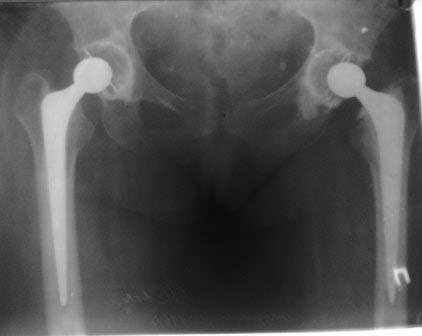

Хочу доложить, недавний случай.

Пациент 60 лет, мужчина. Оперирован в 2007 году, поочередно оперированы два тазобедренных сустава с интервалом в 4 месяца. В 2008 году оперирован на сердце(аорто-коронарное шунтирование).Операция осложнилась инфицированием операционной раны в области грудины, лечился в гнойном отделении.

В конце 2008 года отметил боли в правой паховой области при опоре на правую ногу. На рентген снимках таза с тазобедренными суставами явных признаков нестабильности вертлужного компонента не обнаружено. В 2009 году нейрохирурги его "успешно" прооперировали на L\3-\4 связывая болевой синдром в правой паховой области с наличием грыжи указанного межпозвонкового диска. Состояние только ухудшилось, больной уже не мог долго сидеть, боль прогрессировала . Его в 2009 и 2010 годах смотрел ортопед, делались рентгенснимки, но почему то приходили к выводу что эндопротез справа стабилен. В марте 2011 года я впервые увидел его, через одну неделю после этого был прооперирован. На операции вертлужный компонент при упоре на него инструментом прокручивался во впадине и без труда был извлечен.

Эндопротез Ножка Cerafit компании Ceraver- чашка той же компании.

Расшорошили вертлужную впадину (дебридмент) Заменили чашку,учитывая невозможность полностью исключить инфекционный генез нестабильности, установили вертлужный компонент цементной фиксации (цемент с ванкомицином), поменяли головку из-за изменившихся взаимоотношении между бедренным компонентом и новой чашкой. Рану зашили наглухо. Провели антибактериальную терапию Кубицином. Выписали на 10 сутки после операции. Болевой синдром купирован, пациент радостный, уехал к себе в Калугу. Приедет на контрольный осмотр через месяц.

ниже снимок в 2008 году

далее снимок в 2009 году

далее снимок у меня на приеме

при этом, у этого пациента была СОЭ 20 мм в час, лейкоциты и формула лейкоцитарная в норме. Можно было пунктировать сустав, но мы этого не сделали и оказались правы: при вскрытии сустава на операции, сустав был сухой и жидкость для посева мы бы не получили.

Но все же, мы провели его лечение как инфицированного, учитывая анамнез: нагноение операционной раны грудины, после операции на сердце. К тому, боли в правом тазобедренном суставе он отметил после осложненной операции на сердце.

В дополнение к моему вышеуказанному пациенту. Досылаю послеоперационный снимок, который я не выслал сразу.